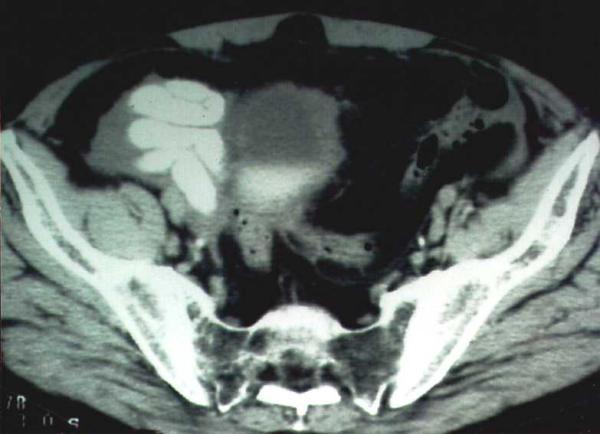

Here, we report a case of isolated colonic tuberculosis where the initial diagnostic workup was suggestive of Crohn's disease. Computed tomography findings however, raised the possibility of colonic tuberculosis and the detection of acid-fast bacilli in biopsy specimens confirmed the diagnosis.

在此,我们报告一例孤立性结肠结核病例,其初始诊断检查提示克罗恩病。然而,计算机断层扫描结果增加了结肠结核的可能性,活检标本中抗酸杆菌的检测证实了诊断。